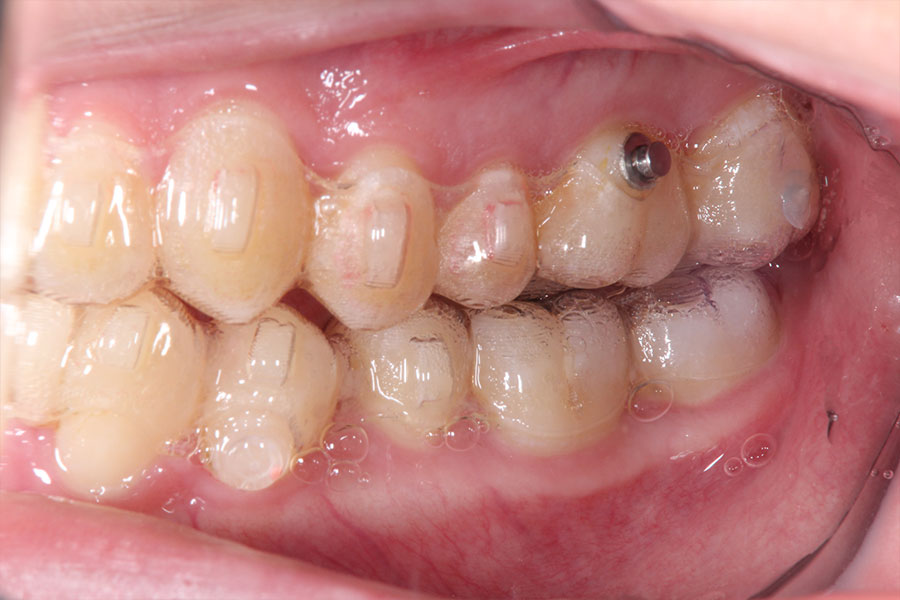

Before -正面-

After -正面-

Before -側面-

After -側面-

| 施術内容 | ワイヤー矯正から、目立ちにくくメタルフリーなインビザラインへ変更しました。 金属アレルギーの不安が軽くなり、取り外しできることで清掃性も向上。見た目も自然で、治療中のストレスが少ない矯正方法です。 |

|---|---|

| 治療期間 | 2年間 |

| 費用 | インビザラインフル 767,800円 リテーナー 30,000円 |

| リスク・副作用 | 治療にともない、歯の破折や歯質の削合、場合によっては抜歯が必要となることがあります。また、金属や補綴物を除去する際に、完全に除去できない場合もあります。 |